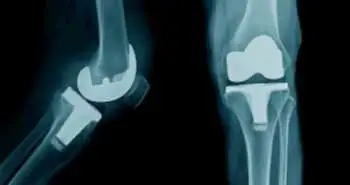

Motor-Sparing Blocks of the knee under the guidance of ultrasound found to be the best adductor canal block to relieve postoperative pain for TKA patients.

Evident from a randomized blinded study, motor-sparing blocks of knee with long-term analgesic effects present better outcomes as compared to intraoperative standard periarticular infiltration in patients underwent TKA. Pain following total knee arthroplasty (TKA) is serious and can inhibit rehabilitation. Motor-sparing analgesic techniques such as periarticular infiltrations and adductor canal blocks have been popularized for knee analgesia since they conserve motor strength and permit early mobilization.